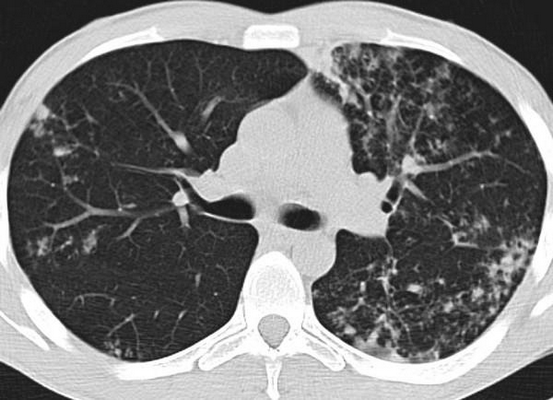

(Слева) При аксиальной КТ с контрастом у пожилого человека без какой-либо симптоматики были выявлены обызвествления в брыжеечных лимфоузлах, которые обычно обнаруживаются у пожилых лиц с микобактериальной кишечной инфекцией, чаще всего в результате употребления непастеризованного молока.

(Справа) При аксиальной КТ с контрастным усилением у пациента с трансплантированной печенью (реципиента) визуализируется выраженное утолщение сальнике, брюшины и брыжейки, а также увеличение брыжеечных лимфоузлов. Также имеется ограниченный асцит (не показан). Туберкулезом пациент был первично заражен в своей родной стране, впоследствии произошла реактивация заболевания с проявлениями в виде туберкулезного перитонита. (Слева) Эта рентгенограмма кишечника, полученная у иммигранта из Индии 25 лет, демонстрирует деформацию терминальных отделов подвздошной и слепой кишки с асимметричным утолщением и уплотнением стенки кишечника, обусловленными туберкулезной инфекцией.

(Справа) На корональных изображениях при КТ с контрастом у этого же пациента визуализируется неравномерное утолщение стенки слепой кишки, которая имеет конусообразный вид (у пациента диагностирован туберкулезный колит).